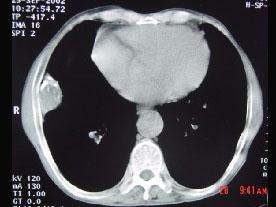

CT图像,最可能诊断为 ( )A.右肺肺占位B.右侧胸膜良性病变C.肋骨病变侵犯胸壁D.膈膨升E.纵隔肿块

问题 CT图像,最可能诊断为 ( )

选项 A.右肺肺占位 B.右侧胸膜良性病变 C.肋骨病变侵犯胸壁 D.膈膨升 E.纵隔肿块

答案 B